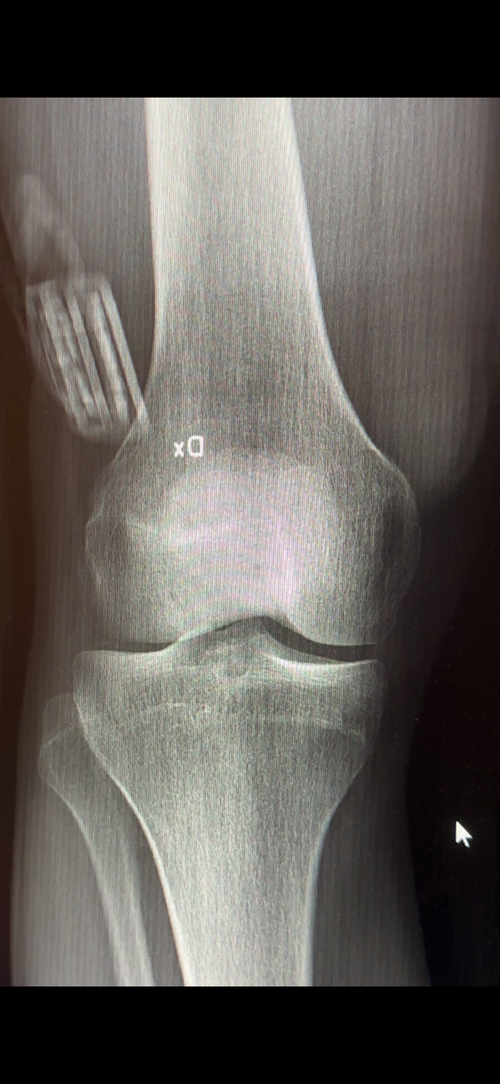

My plates looked like this and I grew about 2cm more in my spine so it would be reasonable to think that you would get at least 1cm in ur legs and 2cm in your spine so at least 3cm I would expect

These are closed